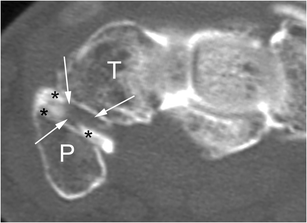

Fig. 2